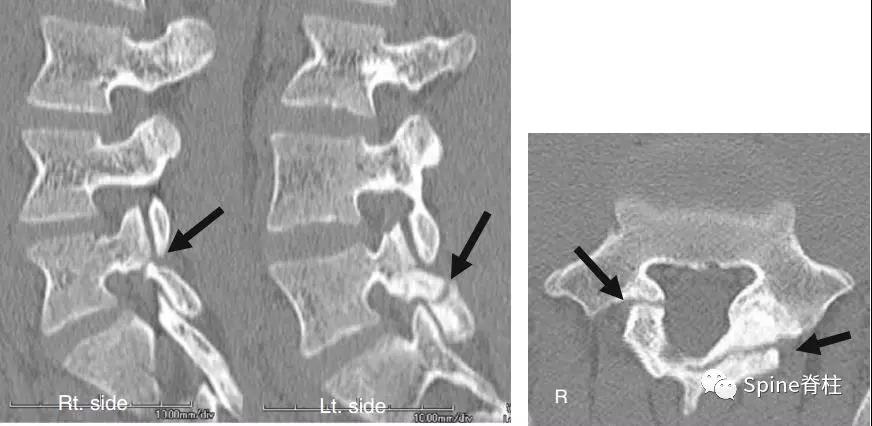

图:L5半椎板裂

17岁芭蕾舞者,腰痛7个月

CT示:左侧为椎板裂(箭头),右侧为峡部裂(箭头)

图:L5半椎板裂15岁篮球运动员,严重腰痛,影响睡眠CT示:左侧为椎板裂(箭头),右侧为峡部裂(箭头)